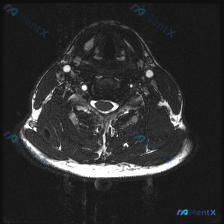

今天碰到一个有意思的情况:临床提示椎间盘病变,只给了一张颈部MRI T2序列轴位图像,咱们一起来理理思路。 病例基本信息 这是一张颈椎下段(推测C5-C6或C6-C7椎间盘水平)的T2轴位MRI,我们先读片: 1. 脊髓:信号均匀,没有明显异常高信号水肿或低信号出血,形态正常 2. 脑脊液:T2高信...